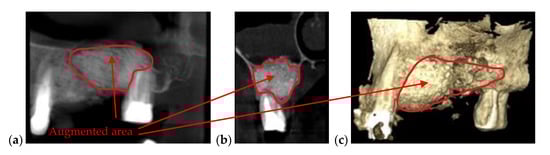

| Bone issues assessment | Accurate investigations of bone density and quantity assessment on 3D CBCT images (see the example in Figure 3) | Cannot penetrate through the bone more than 1 to 2 mm |